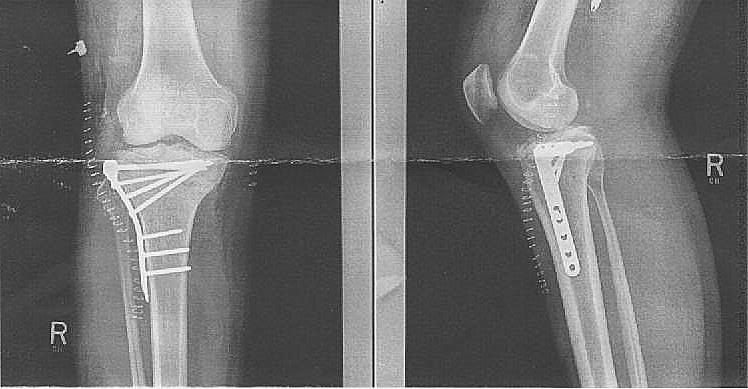

I had a tibial plateau fracture. Surgery with a plate and 10 screws to repair.